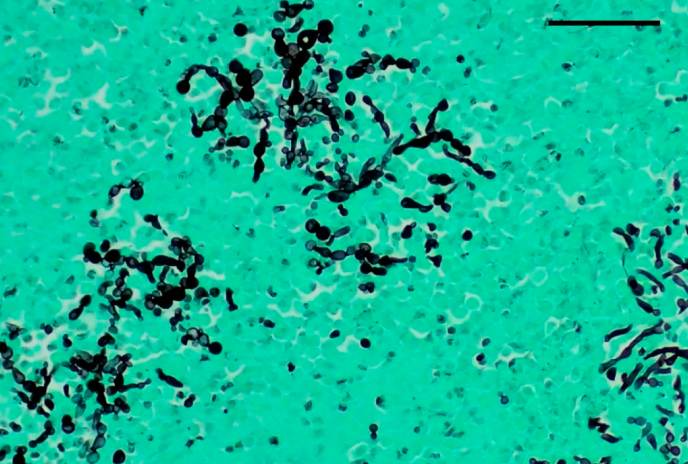

Tissue diagnosis of invasive candidiasis relies on special stains to highlight fungal elements in tissue specimens:

| Stain | Appearance |

|---|---|

| PAS (Periodic Acid–Schiff) | Magenta yeast and pseudohyphae |

| GMS (Gomori Methenamine Silver) | Black yeast and hyphae against green background |

Culture and Histopathology:

- BAL culture: Sensitivity 50-60%

- Tissue biopsy: Septate hyphae with acute-angle (45°) branching

- PAS and GMS stains highlight fungal elements